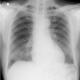

ALO Dokter, saya ada pasien laki-laki usia 78 tahun datang dengan keluhan pusing yang dirasa semakin memberat 2 hari SMRS, muncul tiba-tiba dan pasien mengeluhkan hampir pingsan karena pandangannya terasa gelap selama beberapa detik. Saat ini juga mengeluhkan sesak, namun sesak muncul hilang timbul. Pasien sudah diketahui memiliki MR severe dan sudah menjalani terapi rutin dengan Sp.JP. Terlampir EKG dan rontgen pasien dibawah. Kira-kira sebagai GP apa tatalaksana yang sebaiknya diberikan untuk pasien ya Dok? Terimakasih sebelumnya